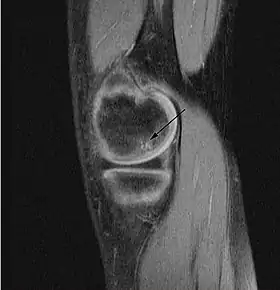

На початковій стадії захворювання можуть виникати відчуття дискомфорту в суглобі і незначний біль. На рентгенологічних знімках ніяких змін, як правило, немає. Основні ознаки захворювання можна визначити на МРТ — значний внутрішньокістковий «набряк» ураженої ділянки кістки. Згодом виникає відповідна реакція суглоба у вигляді синовіту (набряк суглоба) і посилення больових відчуттів.

Далі відмерла ділянка виростків «відвалюється» від стегнової кістки з утворенням хондромного тіла (суглобової миші). Часто внутрішньосуглобове тіло блокує суглоб, потрапляючи між суглобових поверхонь, тим самим додатково пошкоджуючи їх.